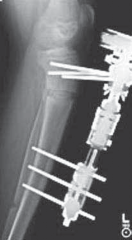

15. On the 14th day, a radiograph should show that the ends of the osteotomized tibia are separated by a distance of about 7 mm (

TECH FIG 4C,D

).

16. Angular correction can now begin. The patient is taught to place the Allen wrench into the primary angulation screw and turn 90 degrees in the direction for angular correction. This 90-degree turn will correct

---

A

B C DE

F

--- TECH FIG 4 • A. The lengthening device is applied. B. A sterile dressing is applied. C,D. Radiographs are taken to verify that there is distraction at the osteotomy site prior to correcting angulation. E,F. Correction is performed until the angulation has been recitified.TECHNIQUES 1 degree of angular deformity and can comfortably be performed four times a day for a correction of about 4 degrees per day until the deformity is corrected (

TECH FIG 4E,F